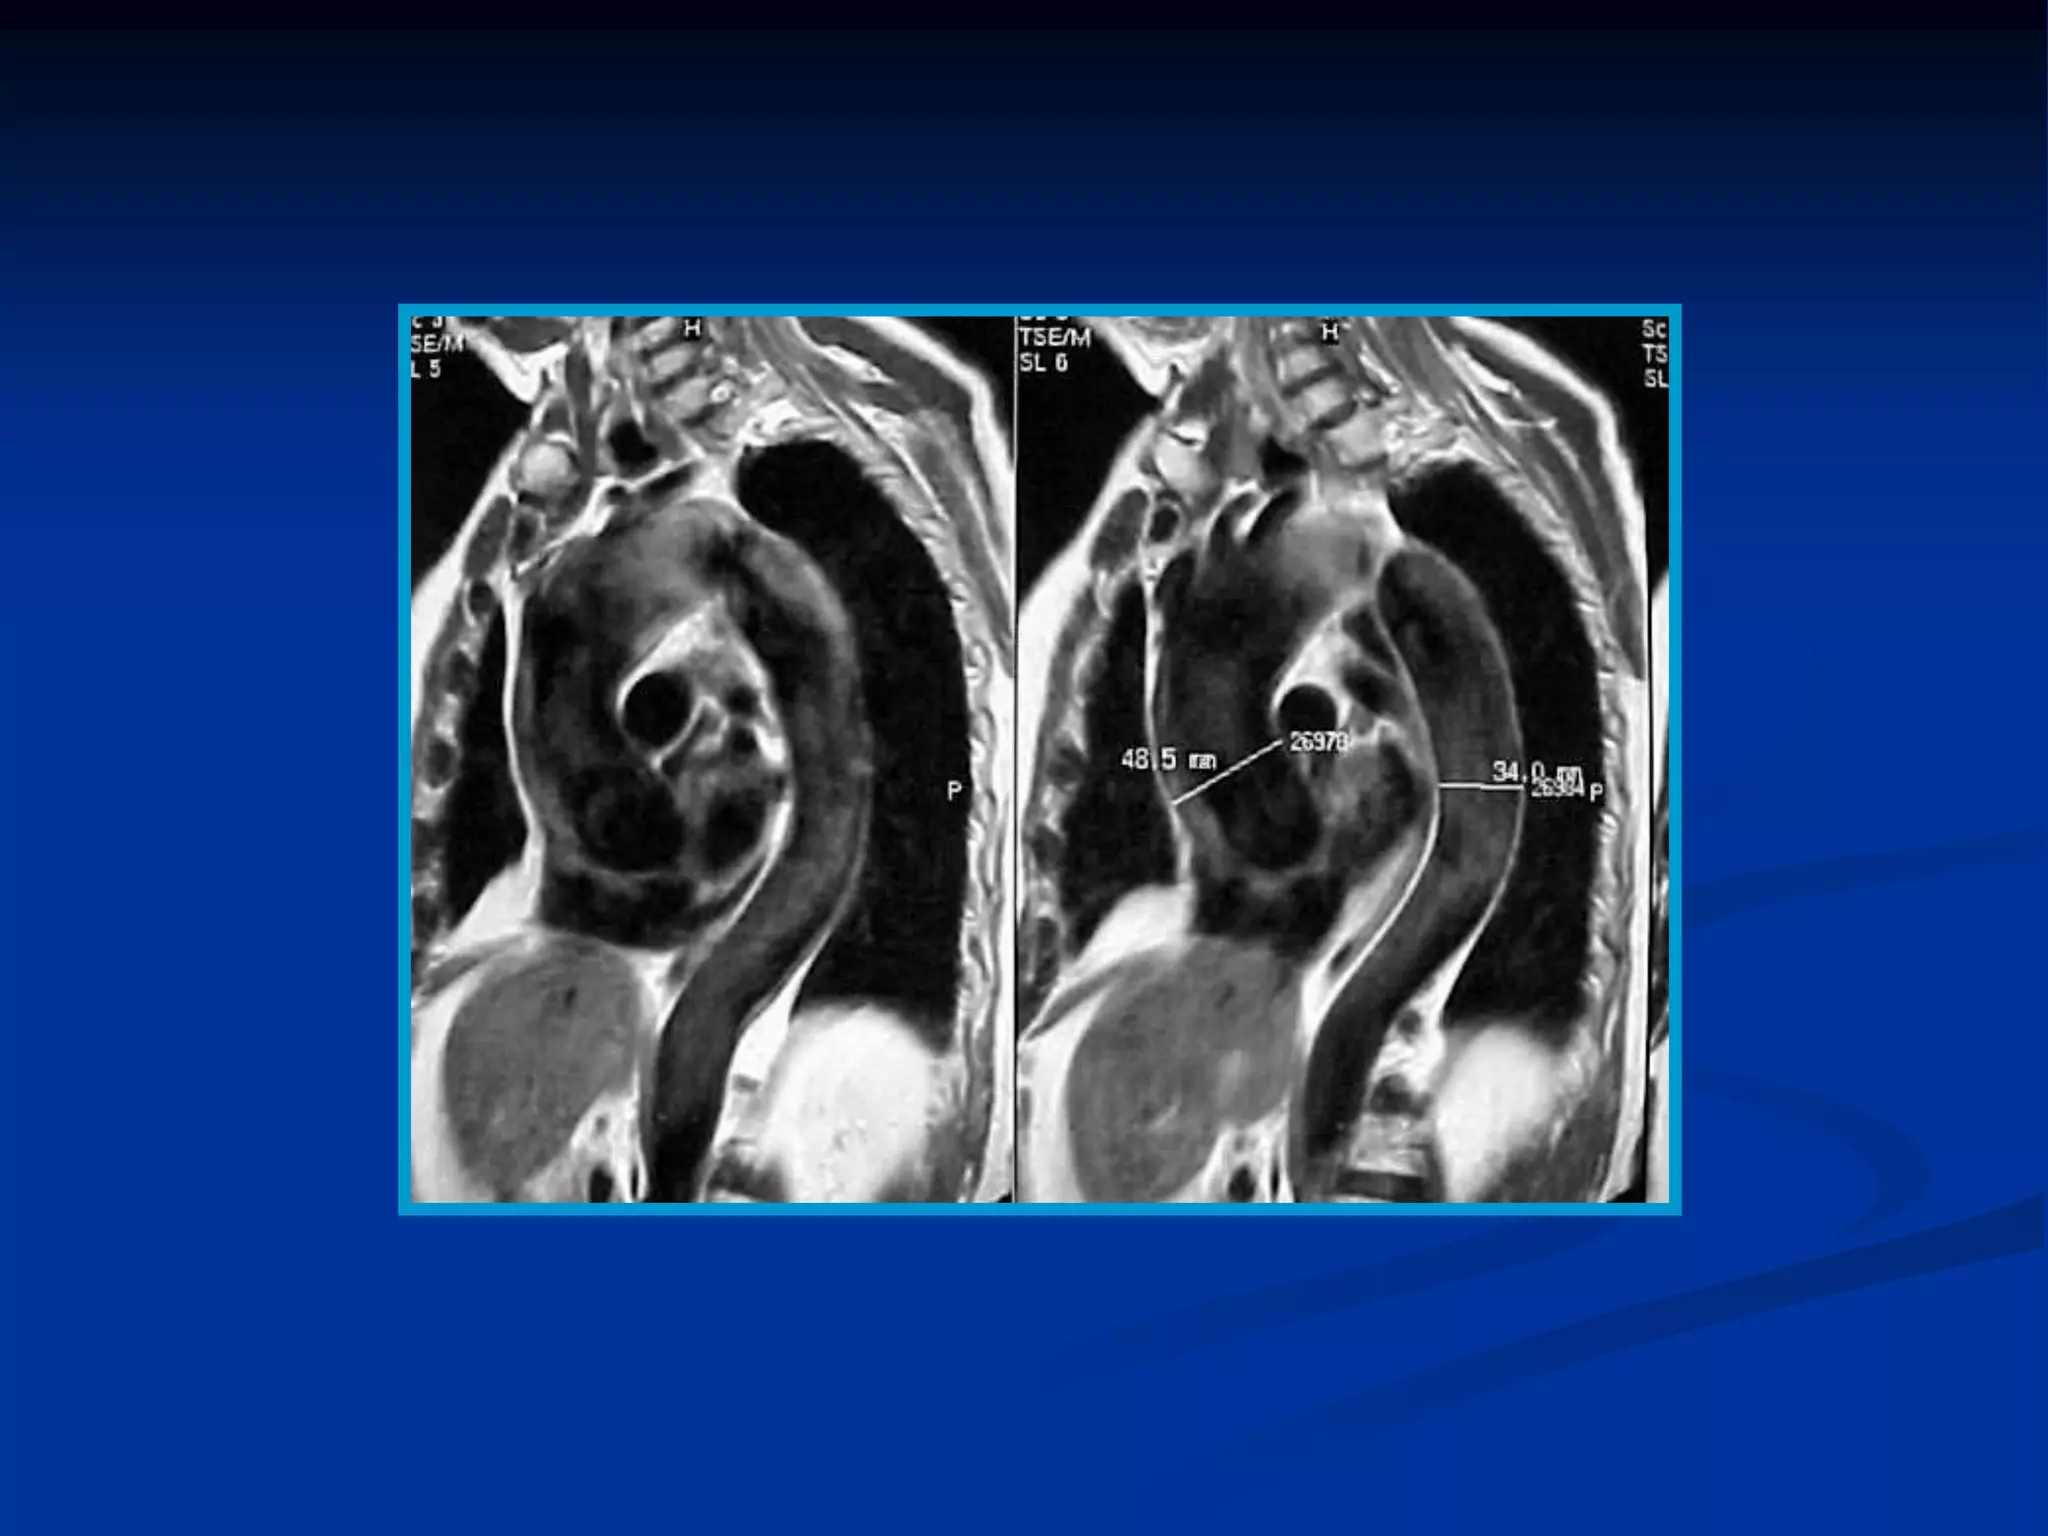

Aneurisma y disección de aorta

Hematoma